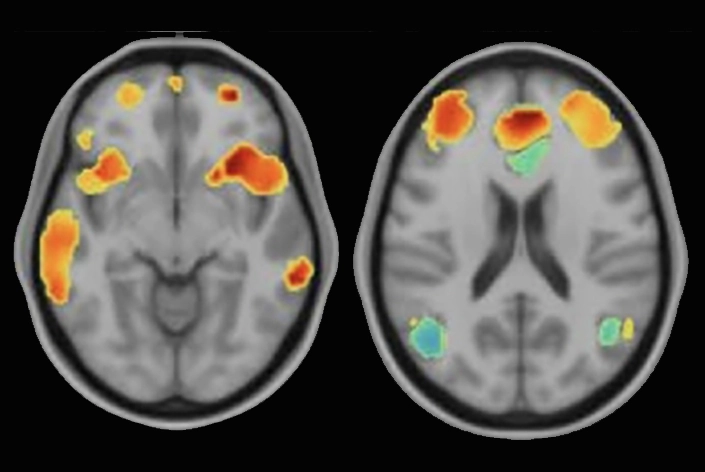

Timing To investigate the impact of TMS on neural activity, the researchers recruited 33 patients diagnosed with treatment-resistant major depressive disorder. Among them, 23 received SNT treatment, while the remaining 10 underwent a sham treatment without magnetic stimulation. Data from these patients were compared with 85 healthy controls without depression. The analysis of fMRI data revealed a significant finding: in patients with depression, the anterior cingulate cortex, responsible for emotions, sent signals to the anterior insula, which integrates bodily sensations. This reverse flow of activity became more pronounced as the severity of depression increased.

The reversed neural activity observed in depressed patients suggested that their moods became primary, influencing how they perceived sensory inputs. However, when these patients received SNT treatment, the researchers noted a shift back to the normal direction of neural activity within a week, coinciding with a reduction in depression symptoms. Intriguingly, individuals with the most severe depression and the most misdirected brain signals experienced the greatest benefits from the treatment, effectively restoring their brain activity to resemble that of healthy individuals.

Diagnosing depression has been a challenge due to the lack of biological markers. However, the findings from this study offer hope for developing a biomarker for depression. The reversed flow of neural activity observed between the anterior cingulate cortex and anterior insula could serve as an important indicator for triaging treatment for depression. By using fMRI data to identify this biomarker, clinicians can determine the likelihood of a patient responding well to SNT treatment, leading to more personalized and effective interventions.